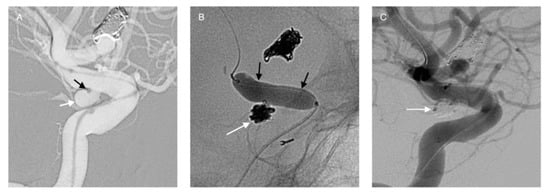

3.2. Balloon-Assisted Coiling (BAC)

- Moret, J.; Cognard, C.; Weill, A.; Castaings, L.; Rey, A. The “remodelling Technique” in the Treatment of Wide Neck Intracranial Aneurysms: Angiographic Results and Clinical Follow-up in 56 Cases. Interv. Neuroradiol. 1997, 3, 21–35. [Google Scholar] [CrossRef]

- Shapiro, M.; Babb, J.; Becske, T.; Nelson, P.K. Safety and Efficacy of Adjunctive Balloon Remodeling during Endovascular Treatment of Intracranial Aneurysms: A Literature Review. Am. J. Neuroradiol. 2008, 29, 1777–1781. [Google Scholar] [CrossRef] [PubMed]

- Pierot, L.; Spelle, L.; Leclerc, X.; Cognard, C.; Bonafé, A.; Moret, J. Endovascular Treatment of Unruptured Intracranial Aneurysms: Comparison of Safety of Remodeling Technique and Standard Treatment with Coils. Radiology 2009, 251, 846–855. [Google Scholar] [CrossRef] [PubMed]

- Sluzewski, M.; Van Rooij, W.J.; Beute, G.N.; Nijssen, P.C. Balloon-Assisted Coil Embolization of Intracranial Aneurysms: Incidence, Complications, and Angiography Results. J. Neurosurg. JNS 2006, 105, 396–399. [Google Scholar] [CrossRef]